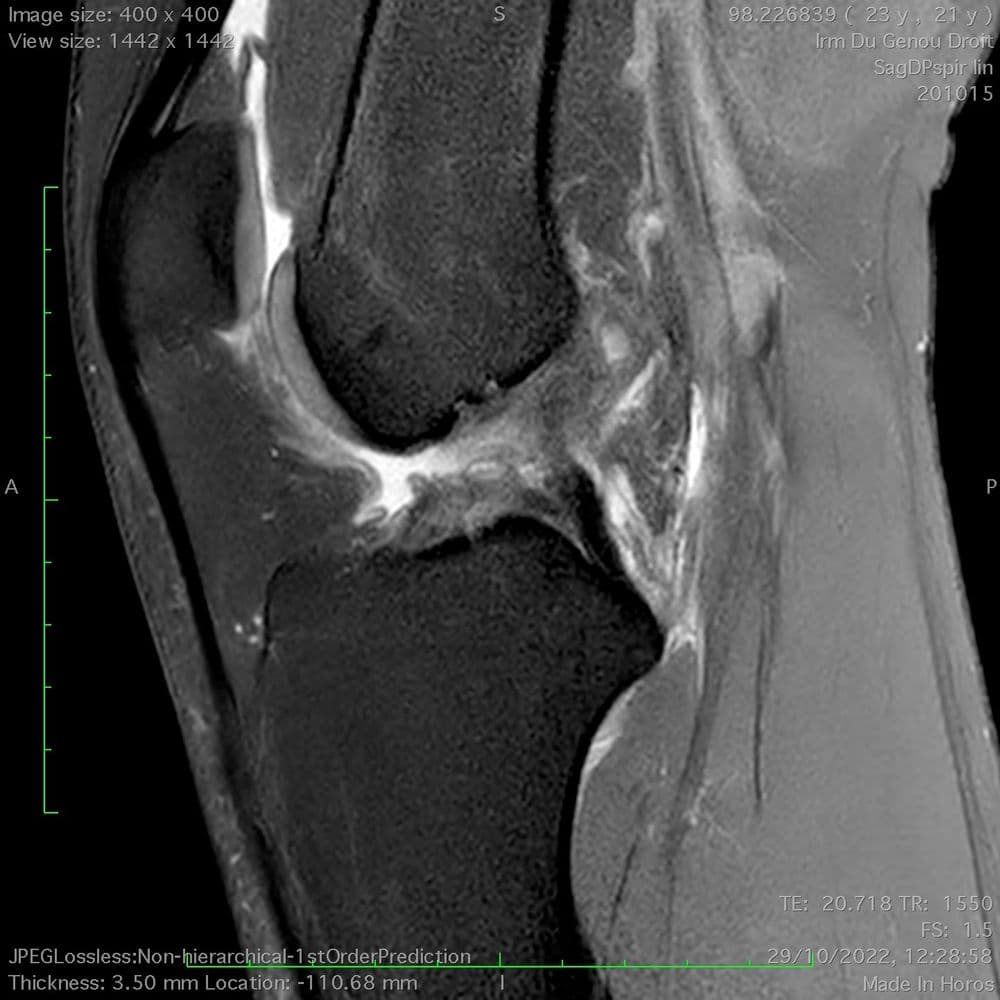

Patient de 33 ans, douleurs antérieures chroniques avec gonflement. Aspect IRM d'une enthésopathie proximale du tendon patellaire.

MRI